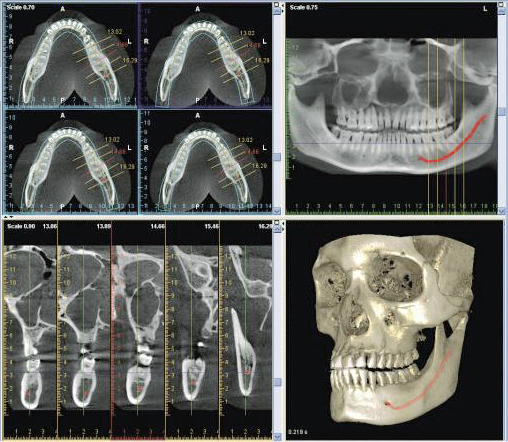

КТ (компьютерная томография) в стоматологии представляет собой технологию выполнения в цифровом формате 3D-объемного снимка челюсти. Один из наиболее объективных и результативных на сегодняшний день методов диагностики в челюстно-лицевой хирургии и стоматологической практике.

Особенности диагностики При минимальной лучевой нагрузке КТ позволяет получить детальное и всестороннее изображение исследуемой области в сравнении с традиционными рентгенологическими снимками. Оборудование для получения 3D-снимка КТ - конусно-лучевой томограф, осуществляющий послойное сканирование исследуемой зоны, обработку полученных цифровых данных и формирование на основе результатов такой обработки трехмерной панорамы зубочелюстной системы пациента.

Возможности диагностики для специалиста широки: - детализация и увеличение модели или ее отдельных участков; - оценка всех ракурсов поэтапно, миллиметр за миллиметром; - сравнение и обследование одновременно двух челюстей или определенного отдельного участка.

Показания 1. Подготовка к плановым хирургическим операциям на челюсти. 2. Оценка аномального строения челюсти, развития, положения зубов перед установкой брекетов. 3. Сложное протезирование - с целью подбора оптимальных протезов пациенту. 4. Аномальный рост третьих моляров ("зубы мудрости"). 5. Болезненность, причину и очаг которой не удается определить. 6. Перелом челюсти, иные травмы. 7. Оценка качества внутриканального лечения. 8. Выявления и подтверждения развития новообразований - как в костной, так и в мягких тканях ротовой полости.

Оптимальные технологии - КТ в имплантологии Верную форму и правильный размер дентального импланта специалист может подобрать лишь в том случае, когда у него есть идеальная модель челюсти пациента. 3D-снимок челюсти, выполненный с помощью КТ, справляется с этой задачей полностью, с максимальной степенью точности. Это положительно влияет не только на продолжительность эксплуатации имплантов, но и на их приживляемость. Кроме того, такая модель позволит определить проблемы, которые не дают о себе знать заранее, но могут стать причиной побочных эффектов и даже невозможности установки импланта. Например, резорбцию кости. Своевременно выявив ее на основе снимка КТ, врач назначит синус-лифтинг во избежание осложнений.

Преимущества компьютерной томографии в стоматологии Главные плюсы процедуры и ее результата, в сравнении с традиционными рентгенографическими исследованиями, заключаются в: - оперативности, минимальном количестве времени на подготовку, проведение процедуры, получение результата; - получении четкого, детального и подробного снимка в высоком качестве; - исключении риска получения "смазанного" неинформативного изображения; - возможности быстро и точно обследовать всю зубочелюстную систему пациента; - безопасности, возможности назначения даже при беременности и лактации; - сохранении информации на флеш-носителе, в почте, возможности впоследствии использования ее для консультации с другими специалистами.